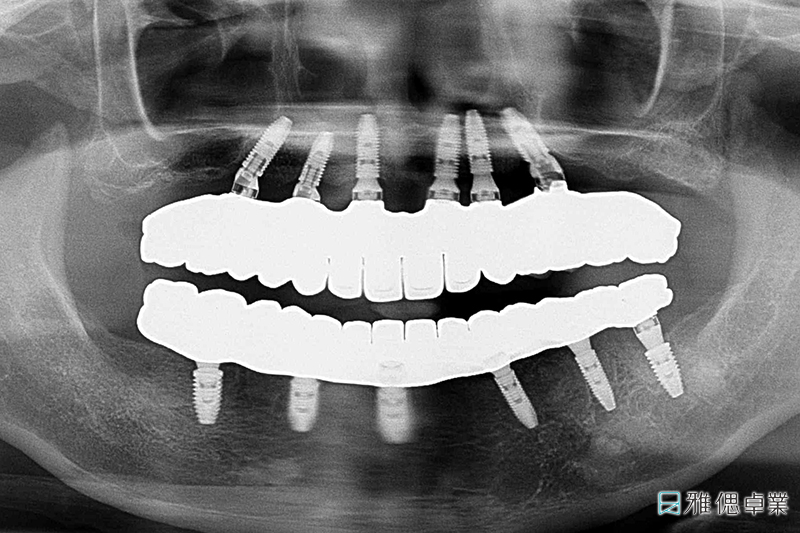

治療過程中的環口X光片

最終完成的環口X光片